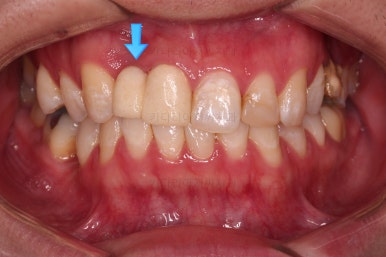

초진 시의 얼굴 모습입니다.

옆라인 양호하고, 치열도 많이 삐뚤진 않았으나 한 쪽으로 쏠려 보이는 양상이었습니다.

그래서 이번 환자분의 목표는 얼굴모습을 바꾸기 보다는 없는 치아를 해넣고 매복치아를 살리는 등의 기능적인 요소에 초점이 맞춰진 치료였습니다.

장치를 부착한 모습입니다.

이번 환자분은 자가결찰 세라믹(엠파워 클리어) 장치를 선택하셨고요.

잔존유치는 발치했고, 앞니 가짜치아는 벗겨내고 새로운 가짜치아를 와이어에 묶어주었습니다.